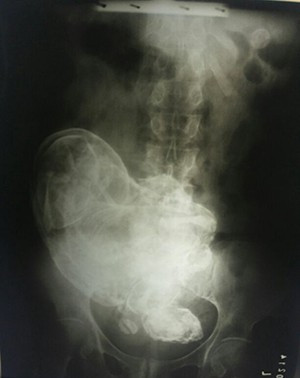

Οι ακτινογραφίες αποκάλυψαν στους γιατρούς, ότι η ηλικιωμένη γυναίκα κουβαλούσε μέσα της ένα έμβρυο ηλικίας περίπου 20-28 εβδομάδων, και διέταξαν τη μεταφορά της στο νοσοκομείο Porto Nacional Hospital για να υποβληθεί σε περαιτέρω εξετάσεις.

«Με τους υπερήχους δεν καταφέραμε να δούμε το έμβρυο, όμως ‘μίλησαν’ οι ακτινογραφίες. Μπορούσαμε να ξεχωρίσουμε το πρόσωπο, τα οστά των χεριών και των ποδιών, τη σπονδυλική του στήλη και τα πλευρά» πρόσθεσε η Dr Kratka.